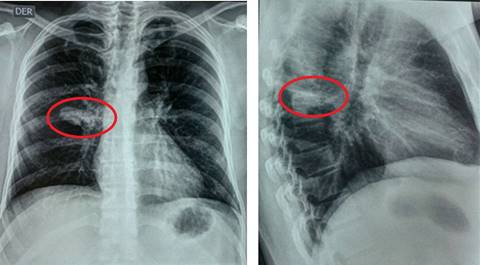

Se le ordenó la realización de una radiografía de tórax (RT) en la que se encontró disminución del tamaño pulmonar izquierdo sin alteraciones parenquimatosas evidentes. En la RT de control, hecha a los tres meses, se observó una atelectasia parahiliar izquierda (Figura 1), tras lo cual se hizo una tomografía computarizada (TAC) de tórax en donde se halló dilatación quística del bronquio para el lóbulo superior izquierdo (LSI) con contenido de tejidos blandos en su interior, que no realzó al contraste, hallazgo compatible con un broncocele, adicionalmente, hiperaireación del segmento apicoposterior del LSI. Los hallazgos sugirieron la presencia de una AB en el segmento apicoposterior del LSI. Se realizó broncoscopia para descartar alteraciones adicionales, sin embargo, lo único evidente fue la disminución del calibre del bronquio segmentario apicoposterior del LSI. Teniendo en cuenta la ausencia de infecciones respiratorias recurrentes relacionadas a la alteración pulmonar, no se consideró necesaria la realización de una intervención quirúrgica de resección y se dio egreso con indicación de seguimiento por el Servicio de Neumología.

Figura 2: Radiografía de tórax anteroposterior y lateral. El círculo rojo muestra una lesión focal «en dedo de guante» parahiliar derecha.